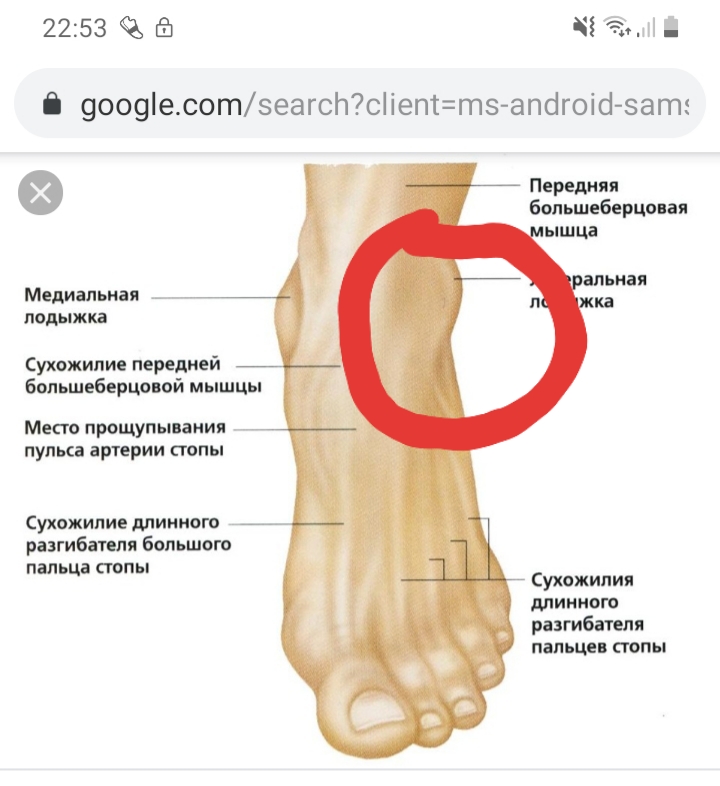

Возможные причины болей в ноге ниже колена и рекомендации